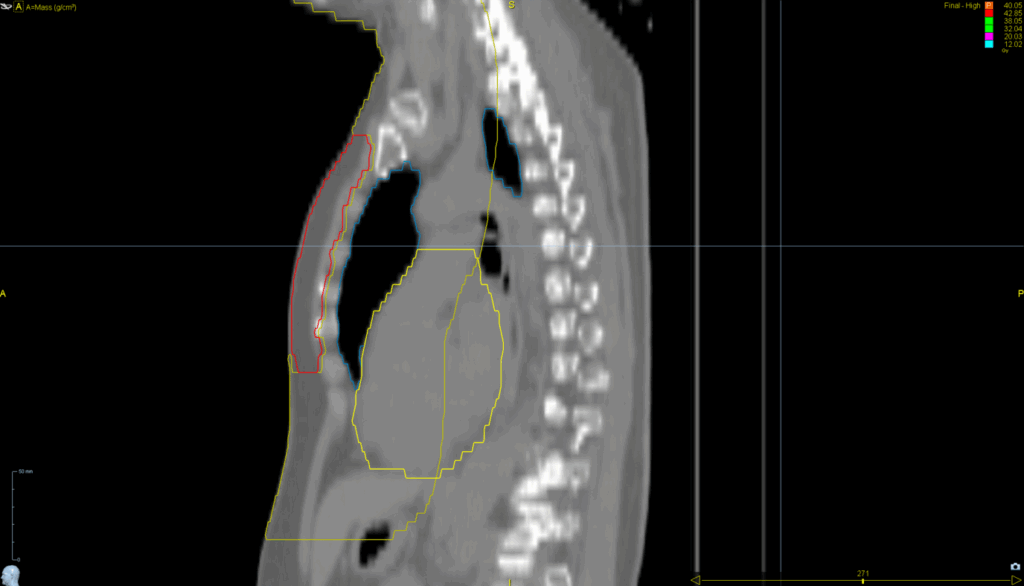

Planning CT Images

TomoDirect™ 2 angles

• VitalHold™

TomoEDGE™ 5cm